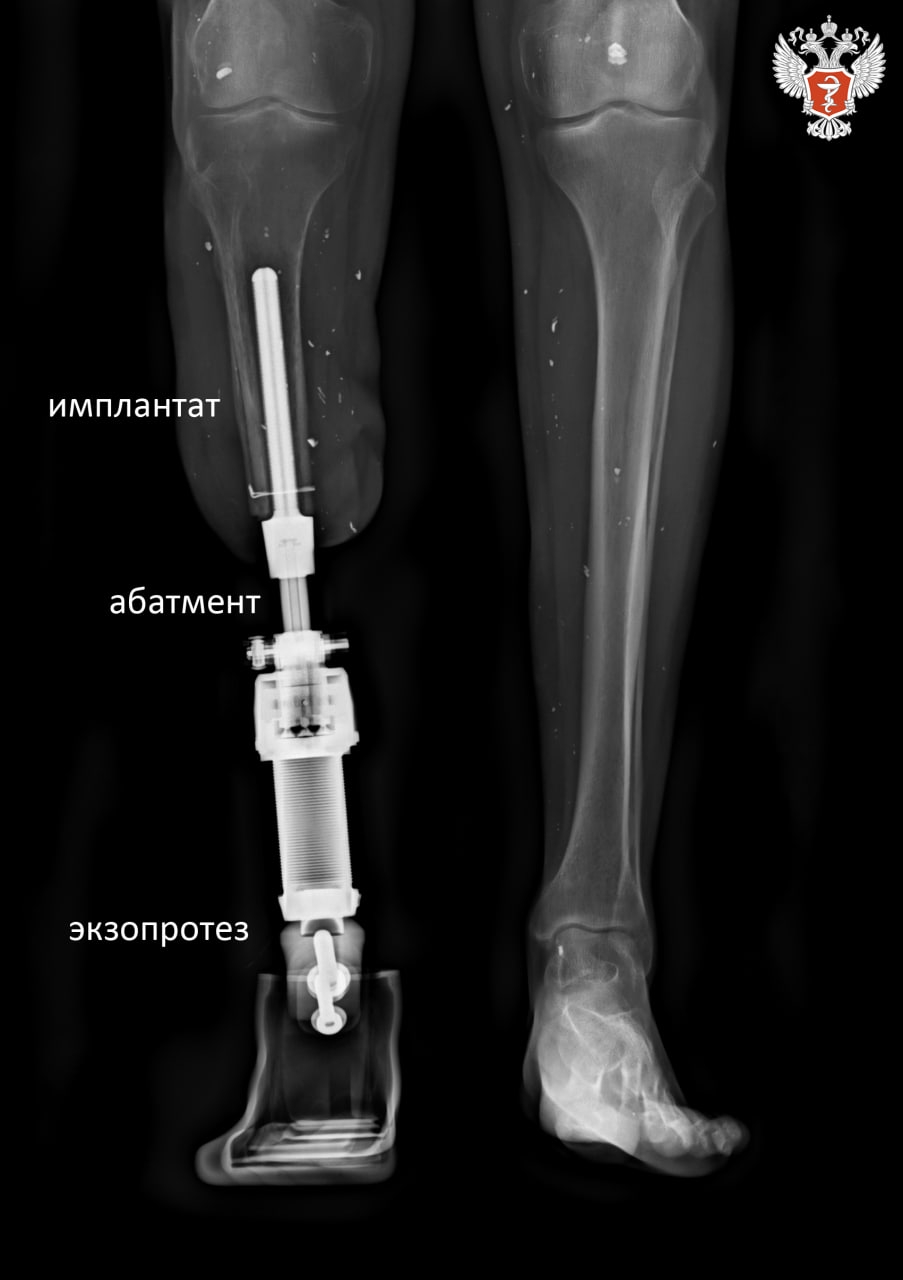

📌 Врачи решили провести протезирование инновационным методом остеоинтеграции — высокотехнологичную операцию, при которой индивидуальный титановый имплантат вживляется в кость, врастает в нее, а через абатмент соединяется с внешним экзопротезом.